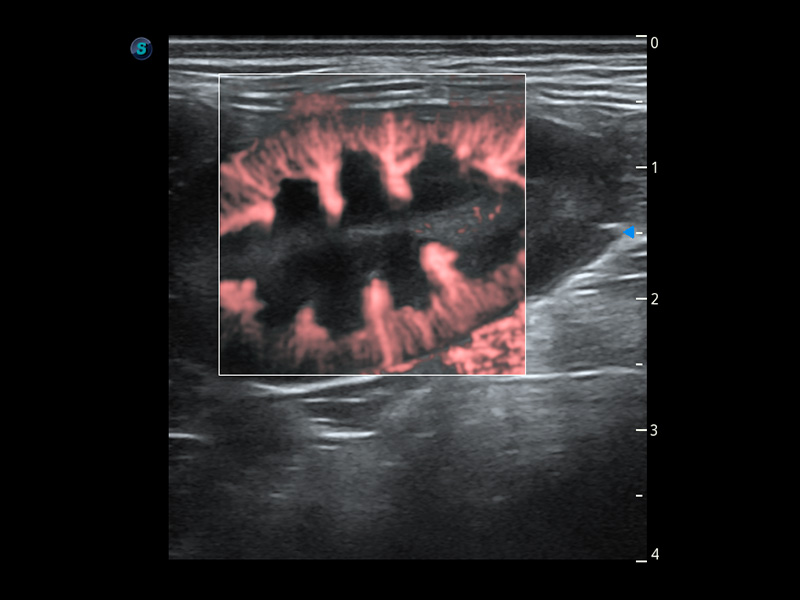

ProPet 60 作为一款高端台式动物超声设备,为动物医生的日常诊断提供了一系列贴合动物临床需求、解决临床实际问题的高级成像功能。凭借全系列高清探头,满足医生对腹部、心脏、生殖、浅表、肌骨等成像的所有需求,切实帮助您提升检查效率,提高诊断信心。

动物是人类最亲密的朋友和最值得信赖的伙伴。竞技宝(JJB)官方网站也一直致力于探索动物专用的超声影像解决方案。 全新推出的ProPet系列,是竞技宝(JJB)官方网站在动物超声影像智能化、专业化、精准化的一次跨越式革新。动物不能用言语来表述自己的不适,通过超声影像,ProPet系列搭建了动物医生与不同物种沟通的“桥梁”,为动物医生注入了“治愈之力”。